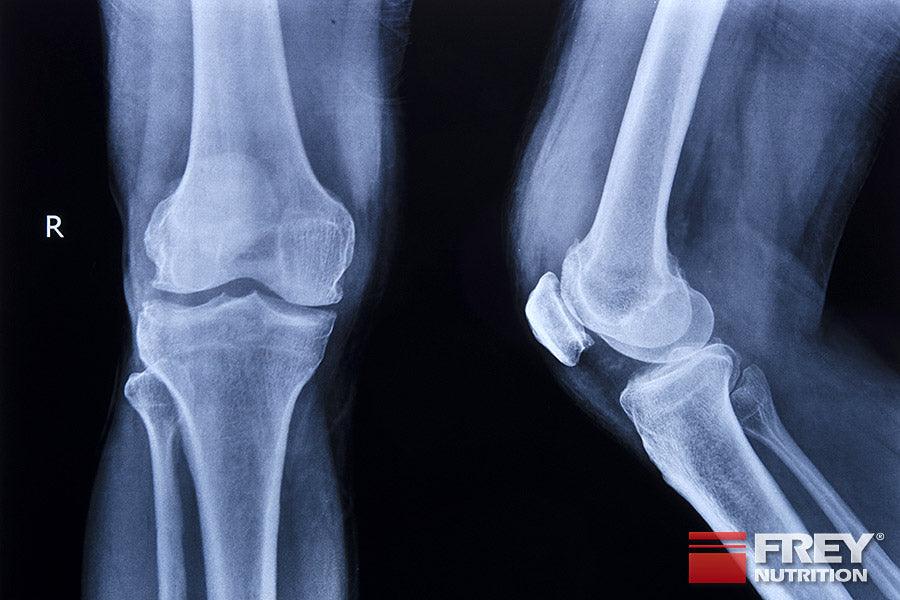

Recent findings with cell cultures of bone cells (osteoblasts) and embryonic bones from rats show that creatine also has a positive effect on bones and cartilage: bone cells and whole bones grow and mineralize significantly better. CREATINE could therefore have a positive effect on the healing of bone fractures and the ingrowth of bone prostheses (artificial hip joints) and also alleviate the course of osteoporosis in old age (I. Gerber, Bone Research Institute, Davos, dissertation (1998) and T. Wallimann, ETH Zurich) .

These findings seem quite understandable considering the fact that the mineralization and formation of cartilage and bone are highly energy-consuming processes, because the creatine kinase system is also present in these cells and can thus improve their cellular energetics. When the creatine kinase system in cartilage and bone cells of experimental animals was inhibited by feeding them with creatine analogues (e.g. guanidinopropionic acid), a clear malformation of the bones was observed, especially in the growth zone. (Funanage et al. 1992) , which underlines the physiological importance of creatine for the normal growth of cartilage and bones. The exact effect of creatine in these areas on humans still needs to be objectively proven in clinical trials. However, those people who take creatine for muscle and nerve strength will certainly be happy to accept an additional positive effect of creatine on their bones.